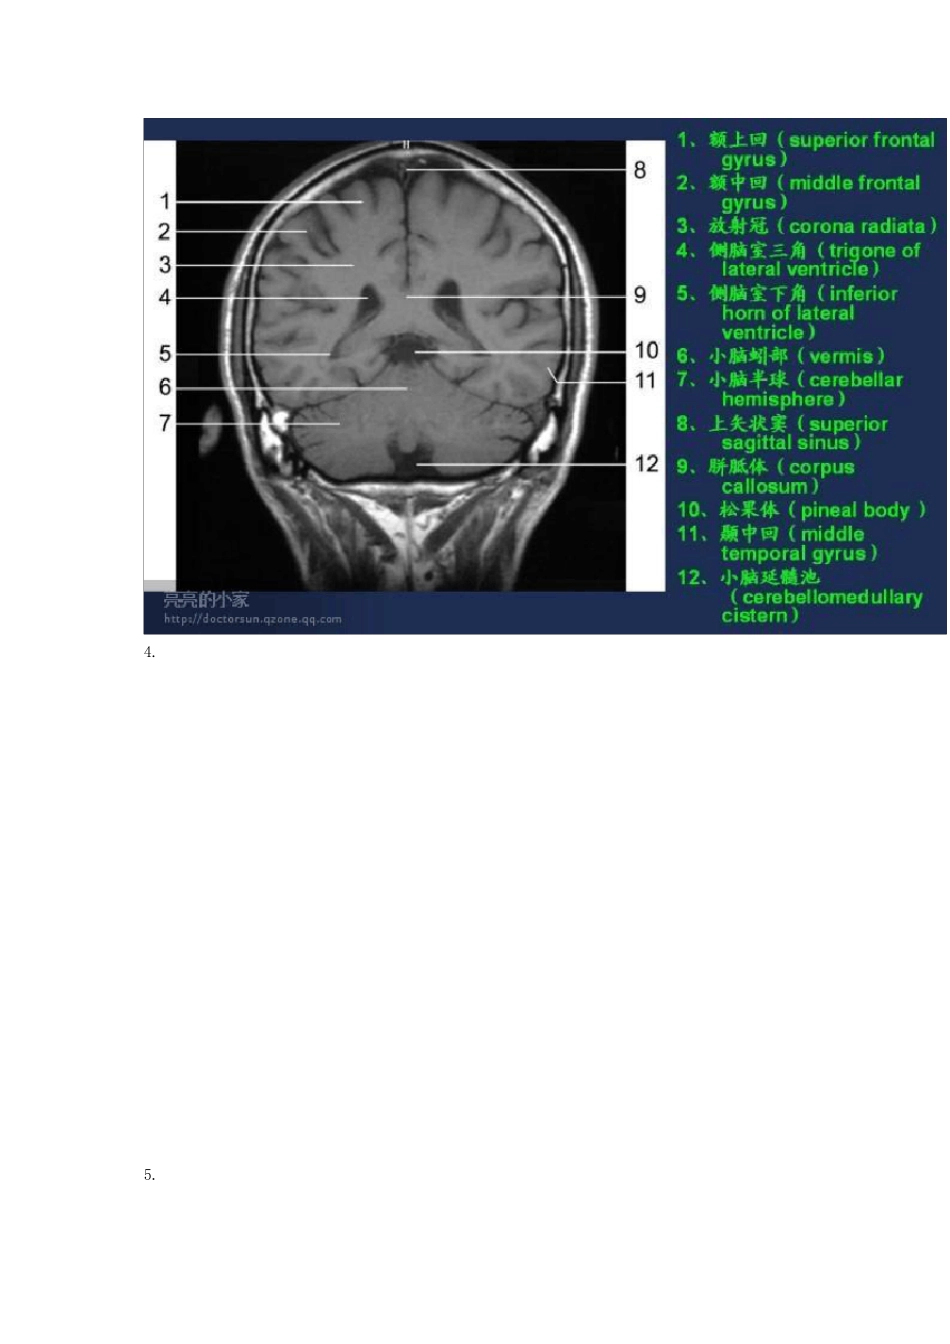

头颅MRI(磁共振成像)断层图谱